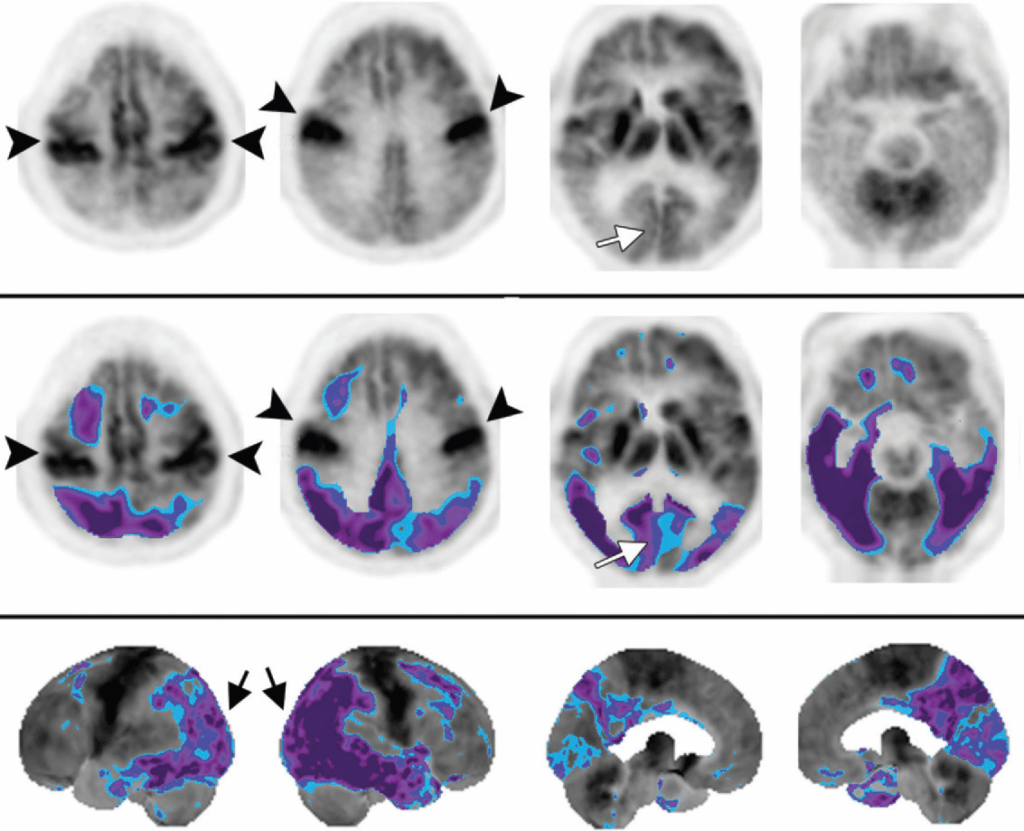

La DLB presenta un pattern di ipometabolismo simile a quello dell’AD, con interessamento parieto-temporale posteriore. Tuttavia, la DLB è caratterizzata da un segno patognomonico che ne permette la differenziazione: il coinvolgimento aggiuntivo dei lobi occipitali, inclusa la corteccia visiva primaria, con un metabolismo relativamente preservato a livello dei lobi temporali mediali e della corteccia cingolata posteriore. Quest’ultima caratteristica prende il nome di “cingulate island sign” (segno dell’isola cingolata). Questa caratteristica è altamente specifica e permette di distinguere la DLB dalla Malattia di Alzheimer, in cui la corteccia visiva è tipicamente risparmiata.